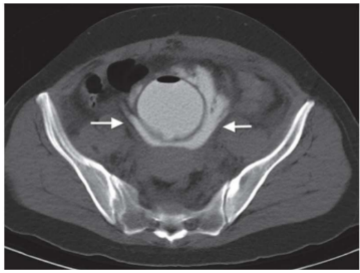

Paciente jovem é vítima de trauma abdominal fechado de alta energia cinética. Durante o atendimento inicial foi visualizado uretrorragia e edema importante de região perineal. Permanece estável hemodinamicamente e realizou a tomografia abaixo após instilação retrógrada de contraste hidrossolúvel por meio de sonda Foley.

Sobre os achados acima, assinale a alternativa correta.